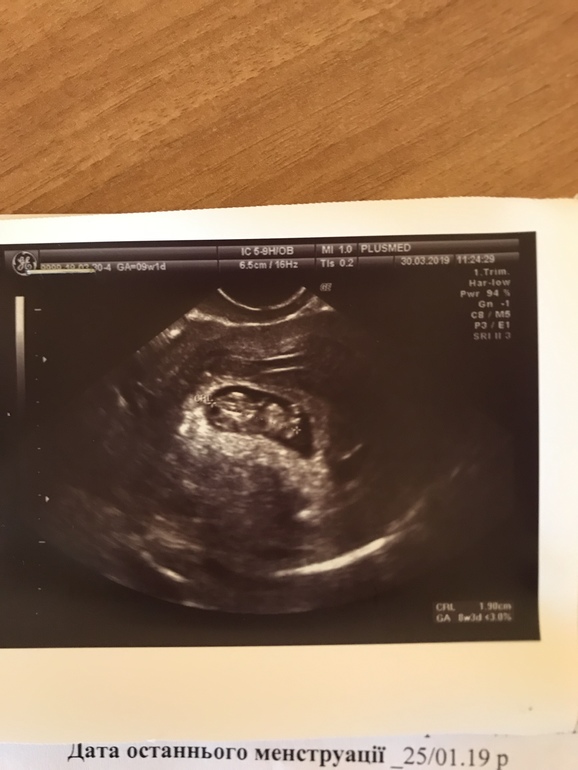

УЗИ, КТГ, доплерЗдравствуйте, девочки. Приболела немного, температура 37,6, насморк, кашель.Была сегодня на УЗИ, срок по месячных 9 недель 1 день, по УЗИ 8 недель 3 дня. КТР 19 мм, ЧСС 167, ПЯ 28 мм, ЖМ 4 мм, толщина хориона 6 мм, ШМ 36 мм. Локализация хориона-задняя стенка матки. Ручки, ножки красиво видно.На передней стенке матки гематома до 5 мм, не связаная с плодом. По анализам крови всё в норме, кроме фибриногена-он 4,3 (норма 2-4), АЧТВ -29,9 ( норма 30-40) и ферритин 34,6 (норма 5-148), по этим вопросам в понедельник иду к гемостазиологу, принимаю кровоостанавливающее, так как постоянные кровотечения. Скажите, пожалуйста, всё ли нормально по УЗИ? Не большое ли отставание в развитии? У меня ЭКО. Фото УЗИ добавляю.